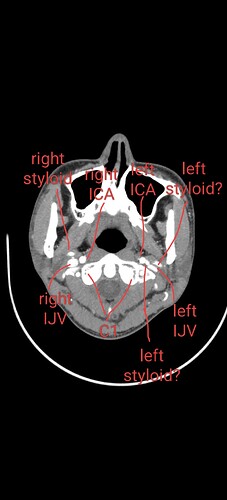

@NoneElongatedStyloid see attached your annotated imaging.

Your left IJV appears to be compressed between your c1 and your styloid. I’mpretty sure your left styloid is the one I have labelled in the top right of the picture, but there is also a white dot between your left ICA and left IJV and I’m not sure what it is. It’s likely another blood vessel or something? Your right side seems pretty okay. That being said, I think your hyoid greater horns are contributing to your symptoms, particularly your right greater horn.

@NoneElongatedStyloid I’m not sure if you saw it, but a week ago I uploaded this annotated image of your greater horns. You can scroll up to see what I had to say about it and why I think it’s causing you problems. I think your right greater horn is worse since it’s touching your right ICA. But I think the left should be removed too.

@NoneElongatedStyloid not sure what you’re referring to when you say “they’re”, do you mean the ICAs? At this level the ICAs and ECAs start coming together to form the carotid sinus, so they start blending together. That’s normal. What’s not normal is your greater horns being as close as they are to the ICAs/ECAs, particularly on your right.